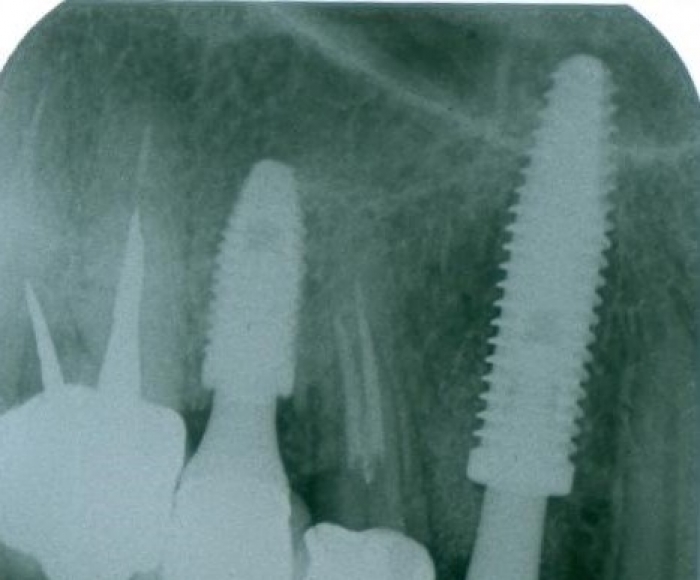

Rx Periapical Pré-cirurgico 03-10-16 - Clínica Cliniface

Rx Periapical Pré-cirurgico 03-10-16